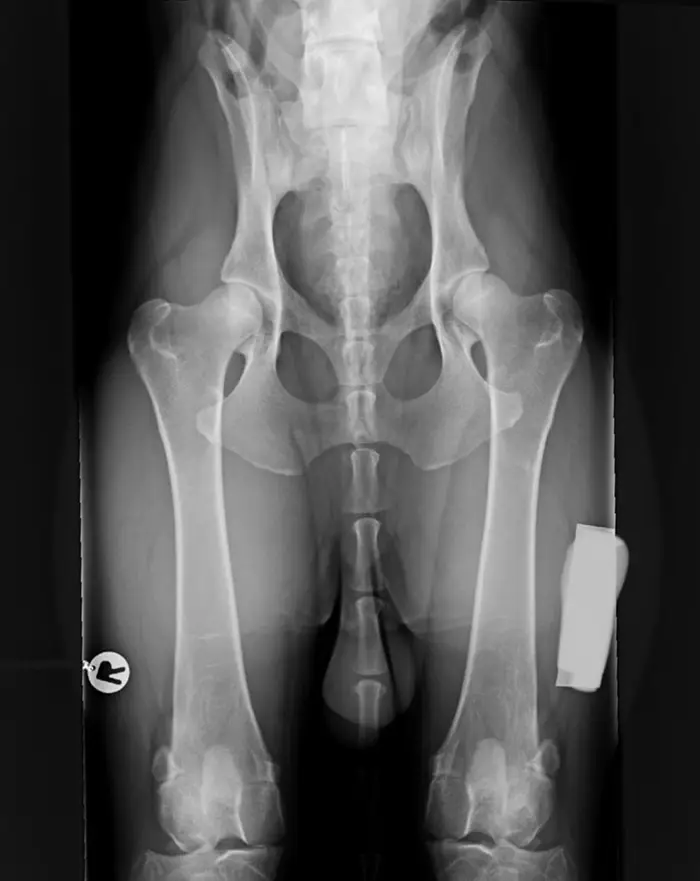

Lonkka 181 €

Koirien viralliset PEVISA-kuvaukset ti 3.3.2026

Taru tekee koko päivän virallisia röntgenkuvauksia. Ei klinikkamaksua ko. päivänä kuvauksista.